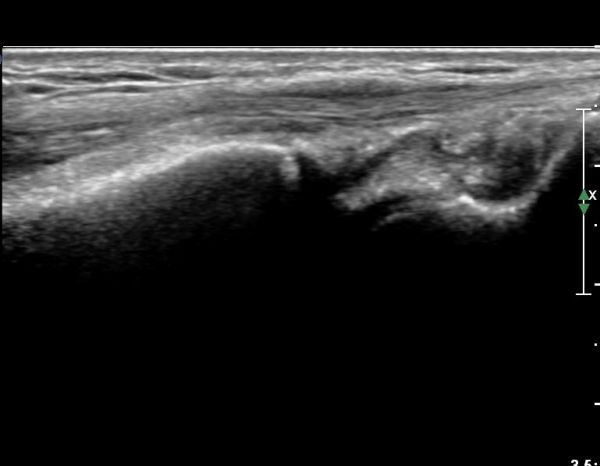

ŽÃÍÀÚ¸¦ ¾à°£ ôÃ÷À¸·Î À̵¿ÇÏ´Ï ¿ä°ñ ¸»´Ü¿¡ ÇÇÁú°ñ ¿¬°á¼º ¼Ò½Ç(loss of cotical continuity)ÀÌ °üÂûµÊ(»çÁø 2, 3).